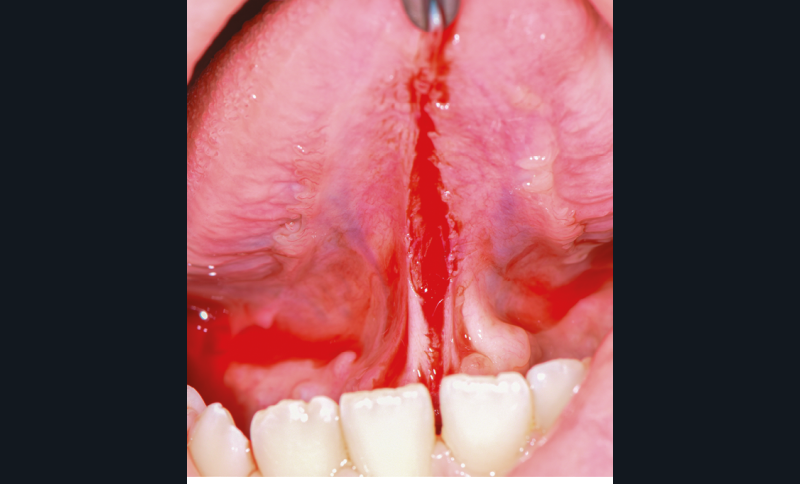

Particularité de la frénectomie linguale

Elle est réalisée lorsqu’il existe une ankyloglossie (anomalie congénitale avec présence d’un frein court).La langue ne peut jouer son rôle de « conformateur buccal » et participer à la morphogenèse du maxillaire supérieur (fig. 4 et 5).